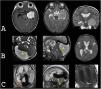

Macrocephaly is a clinical term defined as an occipitofrontal circumference more than two standard deviations above the mean. It is present in 5% of children and is a common indication for imaging studies. There are multiple causes of macrocephaly; most of them are benign. Nevertheless, in some cases, macrocephaly is the clinical manifestation of a condition that requires timely medical and/or surgical treatment. The importance of imaging studies lies in identifying the patients who would benefit from treatment. Children with macrocephaly associated with neurologic alterations, neurocutaneous stigmata, delayed development, or rapid increase of the circumference have a greater risk of having disease. By contrast, parental macrocephaly is predictive of a benign condition. Limiting imaging studies to patients with increased risk makes it possible to optimize resources and reduce unnecessary exposure to tests.